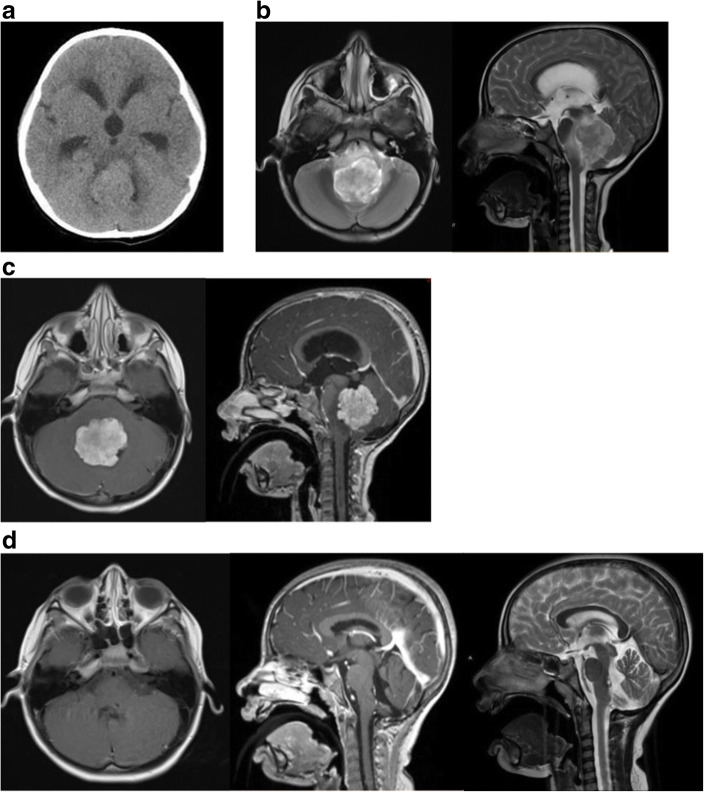

A 5-year-old female presented with 8 months of daily nausea/emesis, loss of body weight, and occasional bifrontal headaches. She began to show increasing unsteady gait for 1 month. Neurological examination showed inability to gaze towards her left side, mild left side esotropia and facial droop and profound truncal ataxia. CT (Fig. 2a) and MR showed a lobular mass in the IV ventricle compressing the left-sided pons causing severe T2 hyperintensity in the dorsal brainstem and cerebellar peduncles (Fig. 2b). MRI with contrast showed a mass with lobulated frond-like margins and intense nearly homogenous enhancement (Fig. 2c).

Fig. 2.

Case 7. a Non-contrast enhanced CT showing an isodense lesion centered in the fourth ventricle with moderate ventriculomegaly. b T2-weighted MR, axial image (left) and sagittal image (right) showing a severe compression on the left-sided floor of the IV ventricle and severe hyperintense changes in the dorsal brainstem and cerebellar peduncle by the IV ventricle tumor. c Contrast enhanced MRI, T1-weighted axial image (left) and sagittal image (right) showing a lobulated homogenously enhancing tumor centered in the IV ventricle. d Postoperative MRI brain; contrast enhanced T1-weighted axial image (left) and sagittal image (center) showing a resolution of IV ventricle tumor with a small residual enhancement on the floor of the IV ventricle, and resolution of brainstem edema on T2-weighted sagittal image (right)

She underwent ETV and EVD for hydrocephalus and then under the same anesthesia, a posterior fossa craniotomy for tumor resection. There were multiple feeding branches noted from the bilateral PICAs, with more feeders noted from the left-sided PICA. The central core of the tumor was densely fibrous and vascular. The floor of fourth ventricle was invaded more to the left side at the pons. The tumor was excised in a piecemeal fashion except for the small portion of tumor invading the floor at the level of the lower pons of the left side.

Postoperative course

Immediate postoperative course was complicated by transient posterior fossa mutism, which completely resolved 4 weeks after the operation. Her cerebellar ataxia also resolved around the same time. However, she had persistent left facial weakness House-Brackmann (HB) stage V/VI, and partial bilateral internuclear ophthalmoplegia. She had a cross-facial nerve animation procedure for persistent left facial weakness 6 months after the operation. At the last follow-up, 24 months after the surgery, her facial paralysis improved to HB stage III. She had persistent partial internuclear ophthalmoplegia without double visions. Follow-up MR shows a stable small lesion on the floor of the fourth ventricle while hyper intense lesion in the brainstem resolved (Fig. 2d).